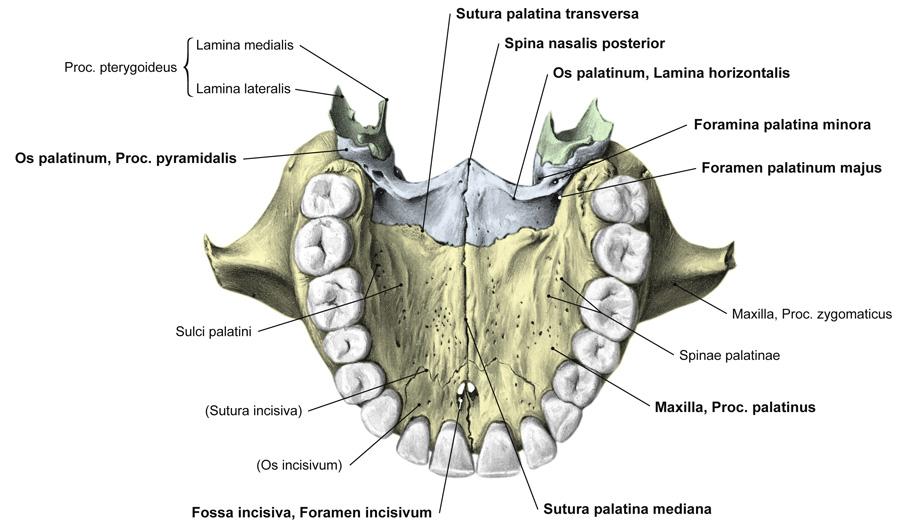

Fig 3.10c: a. maxillaris - sfenomaxillair deel - verhemelte

-

a palatina descendens

-

a palatina maior

aa palatinae minores

|

|